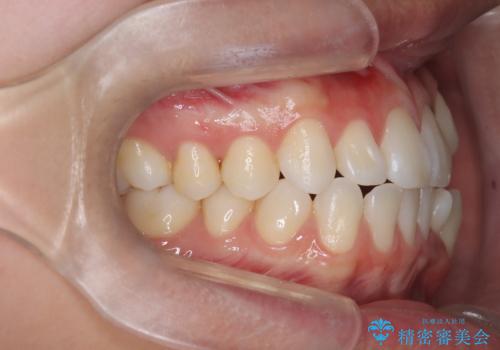

- 治療計画

上下左右の第一小臼歯を抜歯し、クリアブラケット(白い装置)とメタルワイヤーを使用して矯正を開始。初期には犬歯のアーチ内への整列を優先し、中盤からは前歯と奥歯の咬合関係の調整を進めました。審美性に優れた装置を使用したことで、治療中も目立ちにくく、見た目へのストレスが少ない点も評価されています。全体の治療は1年半で完了し、見た目・噛み合わせともに大きく改善。患者本人も「短期間でここまで変わるとは思わなかった」と満足されていました。